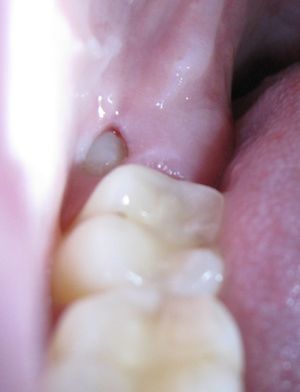

ضرس العقل، أو الضرس الثالث، هو ضرس يقع في أخر الفك، وهو آخر ما ينشأ من الأسنان في الإنسان. ويوجد ضرس عقل واحد في كل ركن من أركان الفم. ويبدأ في الظهور ما بين سن 17 و25.[1] Most adults have four wisdom teeth, but it is possible to have more—in which case they are called supernumerary teeth—or fewer—a condition called hypodontia. ويؤثر نمو ضرس العقل على باقي الأسنان، أو قد يسبب "إعوجاجهم".[2] وعادة ما يتم خلع ضرس العقل عندما يعاني المريض من بعض المشكلات.